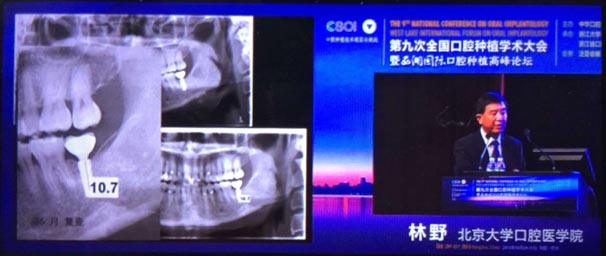

2015年10月29日第九次全國口腔種植學(xué)術(shù)大會暨“西湖國際”口腔種植高峰論壇在浙江省人民大會堂隆重開幕。這是中華口腔種植專業(yè)委員會主辦的兩年一度的全國性學(xué)術(shù)會議,代表了中國口腔種植學(xué)發(fā)展的水平和方向。

會議期間國內(nèi)知名口腔專家針對當(dāng)前口腔種植領(lǐng)域熱點(diǎn)進(jìn)行了精彩的學(xué)術(shù)演講。其中北京大學(xué)口腔醫(yī)學(xué)院林野教授的演講主題是“種植體設(shè)計(jì)及臨床意義”。

威高演講中林野教授對國產(chǎn)品牌WEGO牙種植體系統(tǒng)的設(shè)計(jì)和臨床表現(xiàn)表示肯定,向在座觀眾展示了WEGO牙種植體系統(tǒng)的臨床病例。病例對76枚WEGO牙種植體進(jìn)行了平均21個(gè)月的追蹤觀察,結(jié)果表明WEGO牙種植體脫落、松動、種植體周圍病現(xiàn)象均為0,頸部骨吸收平均值為0.20mmSD值0.07。